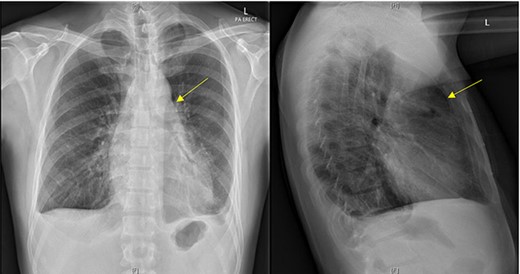

Initial chest X-ray demonstrated lucency over the left heart border and anterior mediastinum suggesting pneumopericardium (Fig. 1). A computed tomography (CT) scan of the chest demonstrated multiple pericardial collections containing loculated gas and fluid with calcification causing stenosis of the superior vena cava. An OPF was suspected (Fig. 2). Bilateral tree-in-bud nodularity reflecting active pulmonary infection with diffuse bronchitis and endobronchial plugging were also present.

CT with water-soluble oral contrast. Trace amount of contrast that extends to the left lateral aspect of the oesophagus representing a thin tract.

An OPF was confirmed on chest CT with water-soluble oral contrast. Endoscopy demonstrated three mucosal defects 31 cm from the incisors (Fig. 3). A fully-covered WallFlex stent (23 × 15 mm, Boston Scientific) was positioned to cover the OPF. The stent was secured proximally to the oesophageal mucosa using resolution clips and distally to the stomach using a 3–0 PDS trans-gastric suture placed laparoscopically. The patient improved and it was decided not to proceed with pericardial drainage.